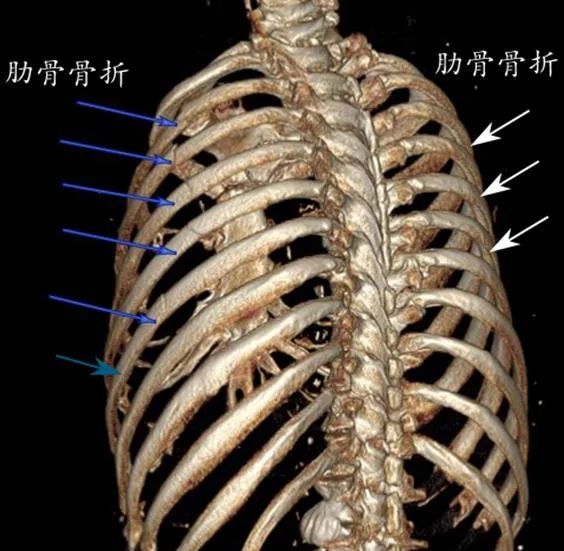

经过胸部CT及肋骨三维重建等检查,显示这是一个重度胸部创伤伴有自身肺部严重疾病的病例。车祸伤致左侧6根肋骨骨折、右侧3根肋骨骨折、肋骨断茬刺破肺产生胸腔积血积气(血气胸)。同时老人自身还有老年性肺气肿、左侧多发性肺大泡,这些肺大泡如同“定时炸弹”随时会破裂造成自发性气胸或血气胸(见图1 、2)。

图1 CT所见双侧多发性肋骨骨折